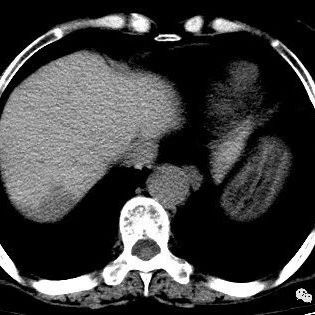

【经典】肝脏占位性疾病的分析思路 影领学苑 · 公众号 · · 5 年前 · |